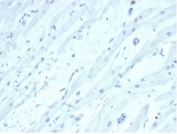

Negative control: IHC staining of FFPE human heart tissue with SATB2 antibody (clone SATB2/7111). HIER: boil tissue sections in pH 9 10mM Tris with 1mM EDTA for 20 min and allow to cool before testing.